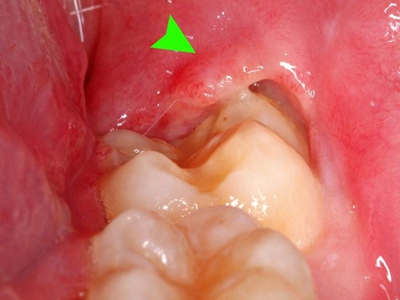

牙龈

红肿

智齿冠周炎右下方的牙龈最内侧红肿图

智齿冠周炎患者右下方的牙龈最内侧有红肿,红肿处有一小创口,可见其内的牙齿,牙齿未完整露出,小创口边缘微微发白,患者自觉有明显疼痛。